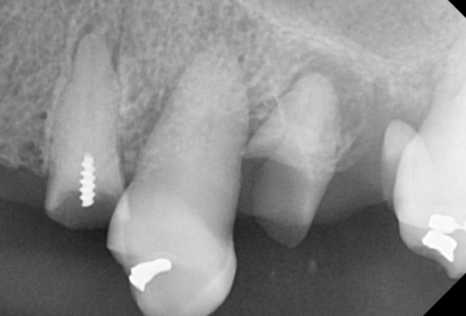

그래서 치아 뿌리 상태를 확인하는

작은 x-ray도 찍고

평가하였습니다.

예후가 좋지 않은 치아는

발치를 하고